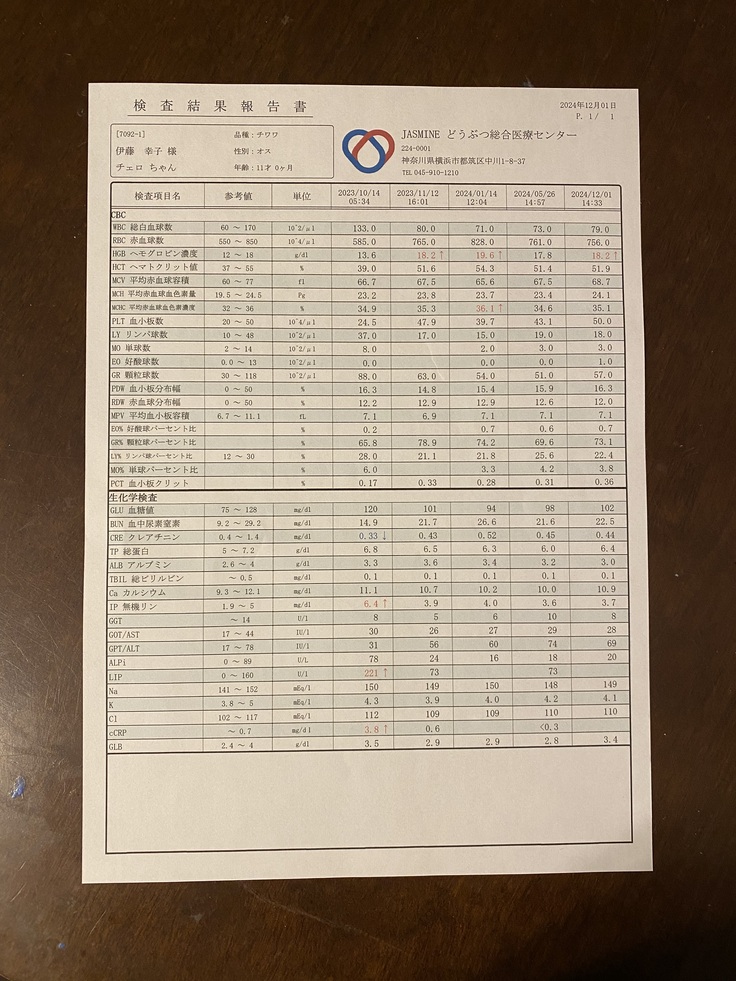

そして、血液検査もGood✨️💮💯

「11歳でこの結果は素晴らしい✨️」とお褒めの言葉をいただきました😊